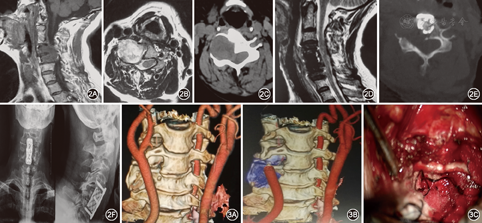

根据肿瘤位置采用后正中入路12例,其中内固定2例;颈前入路3例,内固定1例。(1)后正中入路:术前X线片定位病变节段,全麻后患者俯卧位,半椎板(9例)或全椎板(3例)入路,半椎板入路切除病侧半椎板,全椎板入路截取棘突椎板复合体,均保留棘上韧带和棘间韧带,显微镜下切开硬脊膜,瘤内分块切除内容物,体积缩小后分离肿瘤供瘤动脉及责任神经根,将肿瘤从脊髓上分离切除,先处理椎管内部分,后处理椎管外部分,肿瘤切除完毕后在椎间孔后以人工硬膜覆盖并用生物胶固定防止脑脊液漏。半椎板入路不予固定(图1),全椎板入路行棘突椎板复合体原位回植椎管成形术[5],彻底止血,逐层缝合,不留死腔。2例肿瘤侵犯椎弓根及椎体,予以病侧螺钉内固定以防脊柱失稳。(2)颈前入路:经胸锁乳突肌和颈内动脉鞘内侧钝性分离,避开颈总动脉和颈内静脉,显露椎旁肿瘤和扩大的椎间孔出口,瘤内减压后分离瘤壁与周围血管及神经的粘连,注意保护椎动脉,切除残余肿瘤。其中1例属肖氏分期Ⅳ期,椎体受侵犯严重,肿瘤显微镜下全切后予以椎体重建及固定融合术(图2)。

(1)手术入路:对于此类肿瘤以前学者进行椎管内外分期手术方式,给患者造成创伤大、费用高、治疗时间长、心理负担重等不利影响,本组肿瘤均一期显微切除,减少了创伤,节省了治疗时间及费用。故根据肿瘤的部位及生长方式,选择适当的手术入路,采用显微外科技术是全切除椎管内外沟通性肿瘤的必要措施[7]。本组依据肖氏改良分区分期法,除肿瘤侵犯颈椎前外侧选择颈前入路外,其余均选择后正中入路。①后正中半椎板入路该类肿瘤多为神经鞘瘤,良性肿瘤有完整包膜,沿神经根偏向生长,故半椎板入路能在充分暴露肿瘤的前提下保留棘上韧带、棘间韧带及对侧肌肉,维持脊柱矢状排列,较好的保持脊柱后柱的稳定性,肿瘤切除后无须固定。但肿瘤显露切除困难时为一期全切肿瘤需进一步打开椎间孔后壁,或肿瘤侵犯关节及椎体,造成脊柱稳定性受到破坏,必须采用有效的内固定技术。对于椎管外肿瘤>4 cm,或者在冠状面上累及3个以上椎体水平的病变,则不适合应用半椎板入路[8]。本组9例行后正中半椎板入路肿瘤暴露充分,全切肿瘤,椎板切除范围小,7例未予固定,随访观察无脊柱失稳。②后正中全椎板入路+棘突椎板复合体原位回植椎管成形术全椎板入路截取棘突椎板复合体,保留棘上韧带和棘间韧带,术野暴露充分,术后予以复合体回植椎管成形,钛钉钛片固定。椎管重建和近似解剖复位脊柱后柱,最大限度地保留了脊柱的稳定性,但对于累及3个以上椎体水平的病变,脊柱稳定性尚存影响,故笔者建议行辅助脊柱内固定术。本组3例因椎管内肿瘤较大,为术野暴露充分,行此术式,肿瘤一期显微全切。③颈前入路颈前入路能较好地显示神经根、硬脊膜及脊髓的腹侧,同时可有效显露椎动脉等重要血管,对于有椎体侵犯的椎管内外肿瘤具有明显优势[8]。由于椎旁肿瘤沿神经根走行方向生长至前、中、后斜角肌之间,推挤横突孔、椎动脉、颈前内脏鞘和血管鞘[9],后正中入路难以切除椎旁肿瘤,故对于肿瘤凸向前方及椎旁肿瘤较大时适宜采用此术式。本组3例行此术式,肿瘤均一期全切,其中1例肿瘤属肖氏分期Ⅳ期,椎体受侵犯严重,肿瘤显微镜下全切后予以椎体重建及固定融合术。(2)肿瘤切除:显微镜下先行瘤内分块切除内容物,体积缩小后,手术空间增大,用显微器械小心剥离与神经脊髓的粘连,分离肿瘤供瘤动脉及责任神经根,将肿瘤从脊髓上分离切除,先处理椎管内部分,后处理椎管外部分,如无法剥离,可予以切除受累的神经根。肿瘤切除完毕后在椎间孔后以人工硬膜覆盖并用生物胶固定防止脑脊液漏。

此类肿瘤常挤压、包绕椎动脉,因此术前正确评估椎动脉的解剖位置及受累情况非常关键。Wang等[11]术前重建肿瘤、脊髓、椎动脉的三维立体解剖关系以此选择最佳的手术方式,有助于肿瘤的完全切除,血管神经的最小损伤,以及对脊柱稳定性的最大维持。还有学者认为,除了保护椎动脉外,正确理解和管理周围静脉结构对于椎管内外沟通性肿瘤减少术中出血和手术成功至关重要[12]。本组病例术前行CTA显示椎动脉不同程度受累,其中1例肿瘤侵犯椎体严重,破坏横突孔将病侧椎动脉挤压至颈椎前方严重变细近乎闭塞,对侧椎动脉代偿性增粗。一期显微镜下全切肿瘤,椎动脉保护良好,充盈明显(图3)。尽管保留或重建椎动脉是首选,但偶有牺牲一侧椎动脉的情况,应行球囊阻断试验,术中切除肿瘤的同时予以动脉瘤夹夹闭椎动脉[13]。